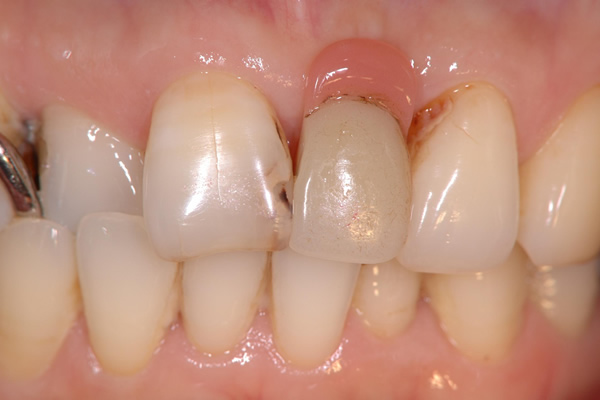

インプラント治療は、インプラントを骨に埋入することではありません。冠(かぶせもの)をして、しっかり咬めるようになることでで初めてインプラント治療をする意味があります。そのためには歯ぐきの治療、かみ合わせの治療など事前に行うべきことがあります。

![]() |

歯科治療では、インプラント治療に限らず見えない部位を診断するために上図のようなレントゲン写真を撮影する必要があります。

当院では、確実な現像・定着・水洗・乾燥・保存処置を行うことで考えられる最高のレントゲン写真の質を確保しています。

しかしながら、立体的な被写体(歯、顎骨など)に対してフィルムやパソコン上に写っているものはあくまで平面的な(2次元的な)像で実物とは異なります。

私たち歯科医師は知識と経験から頭の中で得られた画像を立体的にふくらませているというのが一般的なのです。

そこには像のゆがみや、実際の治療の段階で想定外の口腔内の状態であることが多くあるのも事実です。